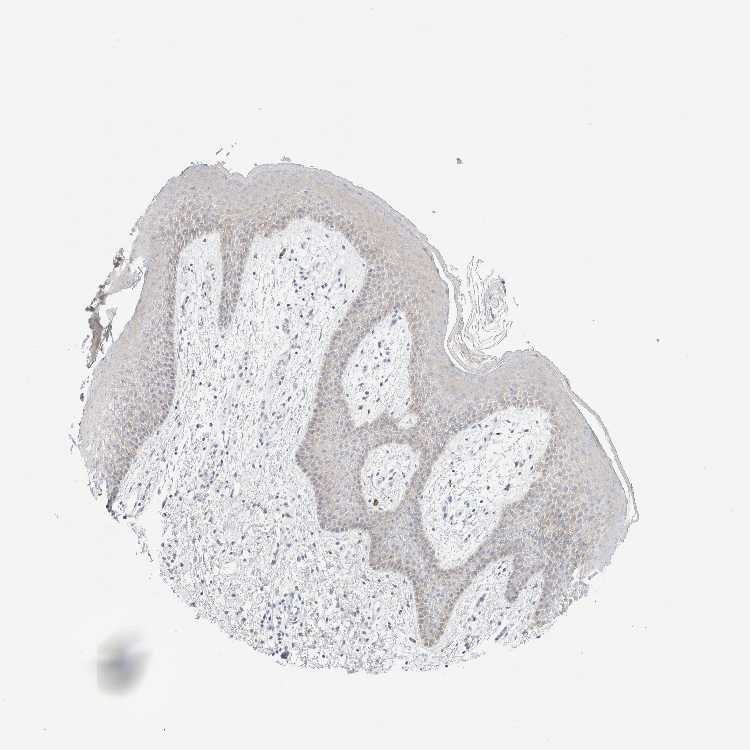

TISSUE PRIMARY DATA SKIN Show tissue menu

SKIN 1 - Antibody stainingi

Antibody staining in the annotated cell types in the current human tissue is reported as not detected, low, medium, or high, based on conventional immunohistochemistry profiling in selected tissues. This score is based on the combination of the staining intensity and fraction of stained cells.

Each image is clickable and will lead to virtual microscopy that enables deeper exploration of all samples and also displays staining intensity scores, fraction scores and subcellular localization as well as patient and tissue information for each sample.

Antibody HPA026110Antibody HPA073304

SKIN 2 - Antibody stainingi